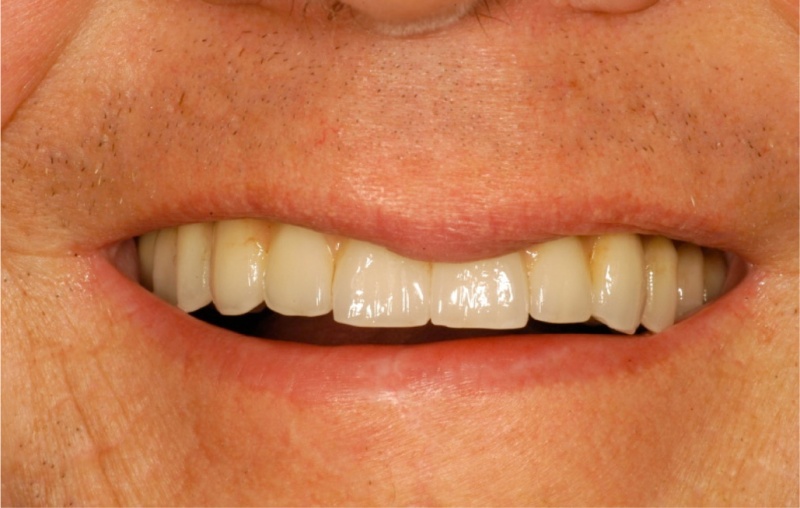

Een patiënt met de ziekte van Parkinson door Dr Defrancq aldus behandeld. De implantaten werden geplaatst onder lokale verdoving en de tanden werden er enkele dagen later vast opgeschroefd .